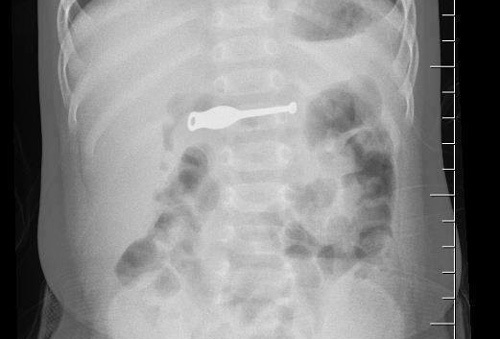

Kết quả chụp X-quang cho thấy, trong dạ dày bệnh nhân có rất nhiều dị vật với các hình dạng khác nhau, đâm thủng cả ruột.

| Ảnh chụp X-quang phát hiện nhiều dị vật trong bụng bệnh nhân |

Ngay lập tức, bệnh nhân được mổ cấp cứu. Sau 3 tiếng, các bác sĩ lấy ra được hàng loạt dị vật từ lá cây, bút bi, thìa nhựa, túi nilon, vỏ kẹo, vỏ thuốc, lò xo...

Theo các bác sĩ, đây là trường hợp cực kỳ hy hữu, chưa từng gặp.